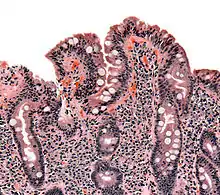

The classic pathology changes of coeliac disease in the small bowel are categorised by the "Marsh classification":[99]

- Marsh stage 0: normal mucosa

- Marsh stage 1: increased number of intra-epithelial lymphocytes (IELs), usually exceeding 20 per 100 enterocytes

- Marsh stage 2: a proliferation of the crypts of Lieberkühn

- Marsh stage 3: partial or complete villous atrophy and crypt hypertrophy[100]

- Marsh stage 4: hypoplasia of the small intestine architecture

Marsh's classification, introduced in 1992, was subsequently modified in 1999 to six stages, where the previous stage 3 was split in three substages.[101] Further studies demonstrated that this system was not always reliable and that the changes observed in coeliac disease could be described in one of three stages:[18][102]

- A representing lymphocytic infiltration with normal villous appearance;

- B1 describing partial villous atrophy; and

- B2 describing complete villous atrophy.

The changes classically improve or reverse after gluten is removed from the diet. However, most guidelines do not recommend a repeat biopsy unless there is no improvement in the symptoms on diet.[40][91] In some cases, a deliberate gluten challenge, followed by a biopsy, may be conducted to confirm or refute the diagnosis. A normal biopsy and normal serology after challenge indicates the diagnosis may have been incorrect.[40]

In untreated coeliac disease, villous atrophy is more common in children younger than three years, but in older children and adults, it is common to find minor intestinal lesions (duodenal lymphocytosis) with normal intestinal villi.[11][25]